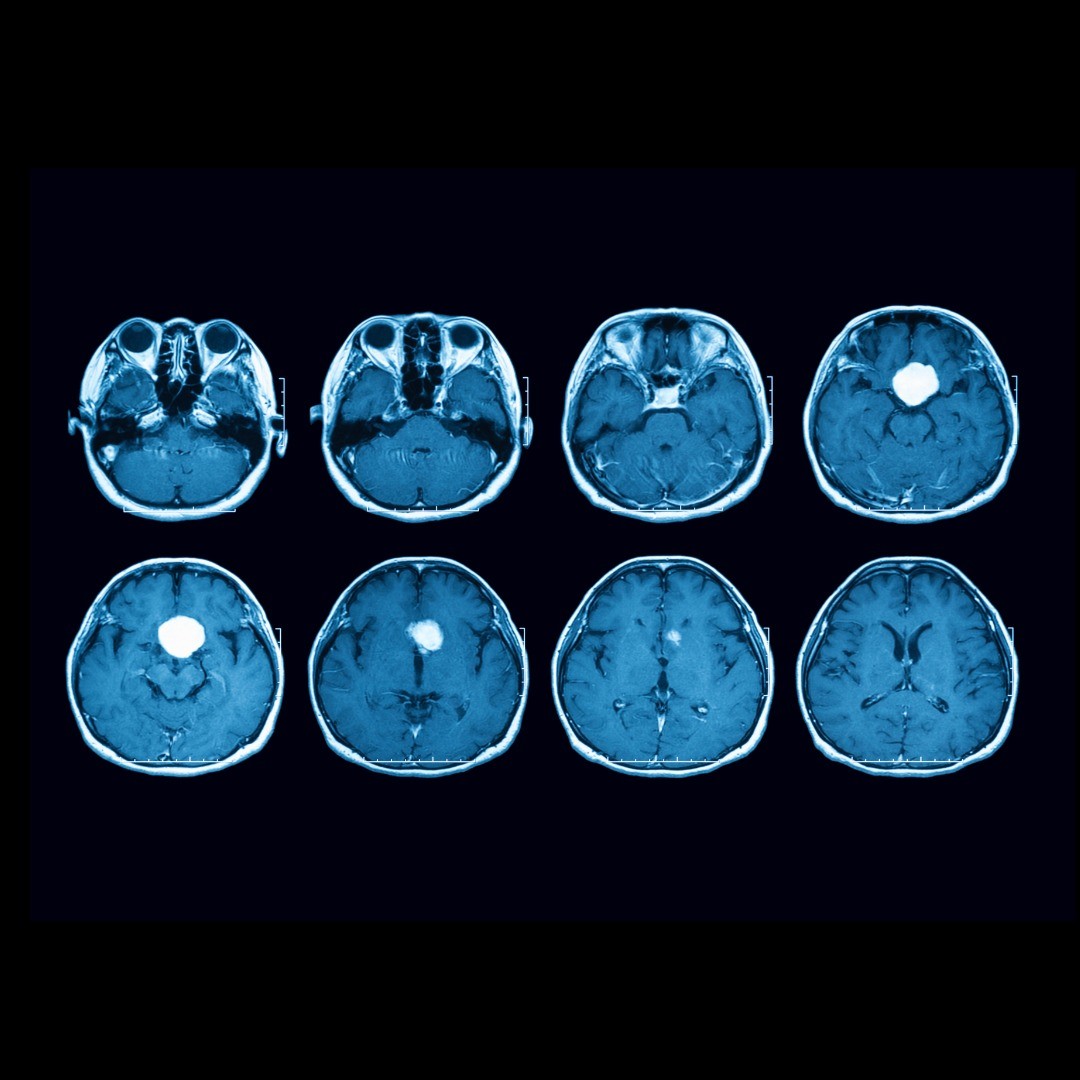

Microvascular decompression is brain surgery to remove pressure (decompression) caused by a very small blood vessel (microvascular) on a cranial nerve, usually the trigeminal nerve.

Candidates for microvascular decompression surgery tend to be younger patients (under age 65) with glossopharyngeal neuralgia, hemifacial spasms or trigeminal neuralgia not caused by multiple sclerosis. Microvascular decompression may be an option if medications and other conservative care treatments have failed to provide relief.